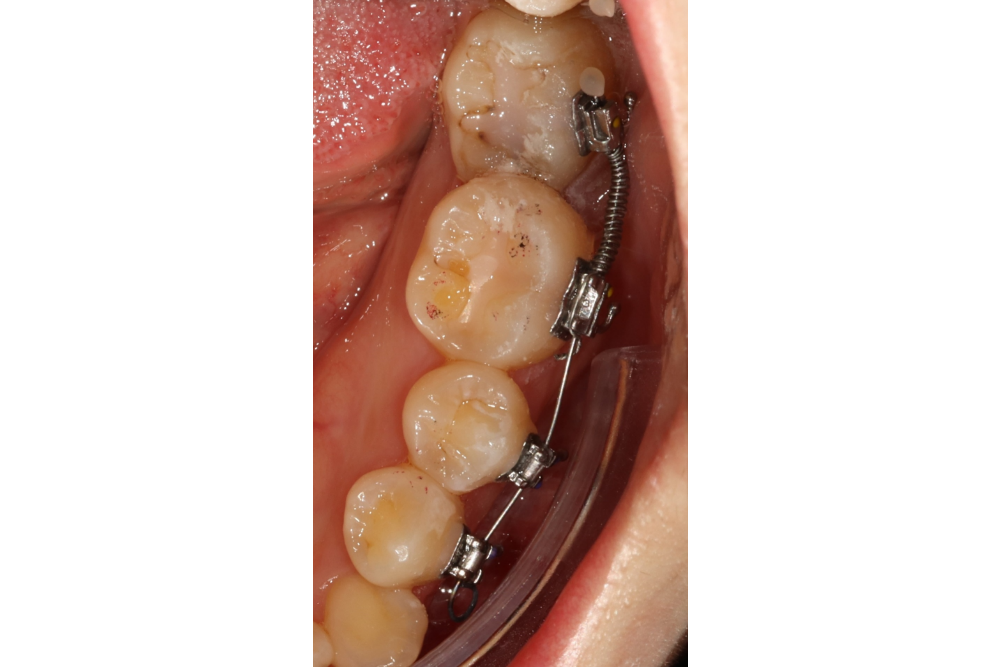

아래쪽 두 번째 어금니(제2대구치)가 선천적으로 없는 결손치로서, 사랑니(제3대구치)가 있으나 앞으로 쓰러져서 잘 안 씹히고 썩어 있습니다.

이런 경우 사랑니를 발치하고 임플란트를 하는 방법도 있으나, 본인 치아를 살리고 싶어하셔서 교정으로 접근하였습니다.

부분교정을 통해 누워있던 사랑니를 세웠으나, 씹는 면에 충치가 있습니다.

교정종료 후 보철치료(인레이)를 통해 씹는 기능을 회복시켰습니다.

누워있던 이가 세워져서 음식물이 더 잘 씹히게 되었습니다.

또한 음식물이 끼지 않게 되어 구강위생관리도 원활하게 되었습니다.